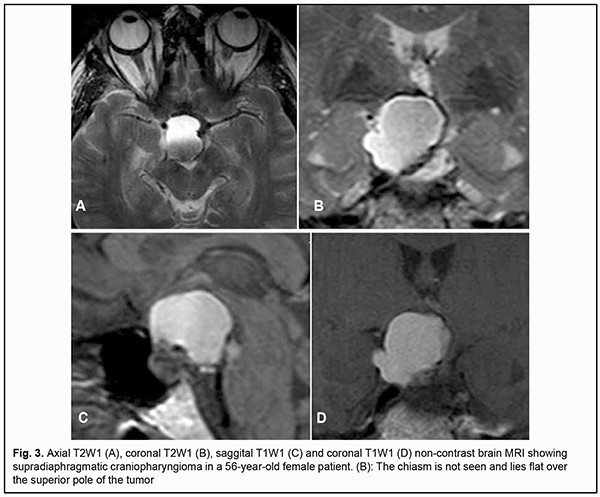

Introduction Skull-base tumors (SBTs) of the middle and anterior fossae typically cause mass effect on the optic nerve/chiasm complex. The most common of these neoplasms are pituitary adenomas, meningiomas and craniopharyngiomas [1, 2, 3, 4]. Chiasmal compression is accompanied by a gradual decrease in visual acuity, bitemporal visual field defects and development of primary descending optic atrophy (OA) [5, 6]. Clinical manifestations of SBTs vary and depend on tumor involvement, nature of growth pattern, and rate of growth. Impaired visual functions are observed in 67.8-83% of patients. Specifically, reduced visual acuity and visual field impairment have been found in 38-68.5% and 68-70%, respectively, of patients [5, 7, 8, 9]. 30-88.9% of cases manifest loss of visual acuity or visual fields [5, 9, 10]. Late-diagnosed but mostly benign processes causing compression of the optic nerve/chiasm complex may result in temporary or permanent visual function loss leading to visual disability. Prolonged chiasmal compression results in the development of OA in 26.7% to 72% of patients, leading to blindness in 3.5% to 25% of cases [4, 10, 11, 12]. Significant or rapidly progressive loss of visual acuity and/or visual fields in the presence of a small tumor may suggest malignancy. Despite progress in neuroimaging techniques, the number of new annually registered cases of primary optic atrophy (OA) associated with SBT and partial or complete loss of visual acuity and/or visual fields, is steadily increasing, making the issue increasingly important [5, 10, 12]. The purpose of the study was to investigate neuroophthalmological symptoms in patients with skull-base tumors. Material and Methods This retrospective study included the records of 500 patients (1000 eyes; 270 (54%) women and 230 (46%) men; aged 14 to 74 years; mean age, 51 ± 0.8 years) who received treatment for SBT and loss of visual acuity and/or visual fields at the Transsphenoidal Neurosurgery Department, Romodanov Neurosurgery Institute, during the period from 2017 through 2019. The inclusion criterion was surgical evidence of SBT. Patients underwent clinical and neurological, eye, and otoneurological examination (a routine otoneurological examination with assessment of cranial nerve function). Instrumental and laboratory studies were conducted. Neuroimaging included sella turcica X-ray study with AXIOM Iconos R100 (Siemens) or Radrex-I (Toshiba) in 72 patients, brain magnetic resonance imaging (MRI) with a 1.5-T MRI system (Intera 1.5T/I system, Philips Medical Systems, Best, the Netherlands) in all patients, and computed tomography (CT). The MRI of brain and pituitary gland were obtained using T1-weighted image (WI) and T2WI. Neuro-ophthalmic examination included best-corrected visual acuity assessment, biomicroscopy, static automated and kinetic perimetry, and direct and indirect ophthalmoscopy. Best-corrected visual acuity was classified as normal (1.0), mild impairment (0.7-0.9), moderate impairment (0.4-0.6), severe impairment (0.1-0.3), and very severe impairment (< 0.1). Static automated perimetry (SAP) was performed with the Centerfield 2 Perimeter (Oculus, Wetzlar, Germany) using the neurological 30-2 threshold test program and Neuro screening program. Aside from defect localization, the arithmetic mean of the sensitivity loss, the mean defect (MD), was used to assess visual field loss severity. Visual field loss severity was classified as “no visual field loss” (Grade 0; normal visual field), mild visual field loss (Grade 1; MD, –2 dB to –4 dB), moderate visual field loss (Grade 2; MD, –4 dB to –12 dB), severe visual field loss (Grade 3; MD, –12 dB to –20 dB), and very severe visual field loss (Grade 4; MD, worse than –20 dB). The visual field loss was classified as very severe if it was not possible to assess visual fields due to the extremely poor visual function. A chiasmal syndrome was considered symmetric if both eyes had the same grade of visual field loss. In addition, a chiasmal syndrome was considered asymmetric if the difference between eyes in grade of visual field loss severity was 1, and it was considered markedly asymmetric if the difference was 2 or greater. Eye movements in each of the four directions of gaze were assessed. Visual acuity was assessed with a diaphragm if there was mydriasis caused by oculomotor nerve palsy. This study followed the ethical standards stated in the Declaration of Helsinki and was approved by the Local Ethics Committee of the Romodanov Institute. Written informed consent was obtained from all individuals enrolled in the study. Results are presented as the mean and standard deviation (M ± SD). Student’s unpaired t test was used to determine differences between independent groups. The level of significance p ≤ 0.05 was assumed. Results and Discussion Loss of visual acuity and/or visual fields was found in 500 (100%) patients. Pituitary adenoma (PA) was the most common tumor-causing loss of visual acuity or visual fields (420 patients; 84%; Fig. 1), followed by sella turcica meningioma (35 patients; 7%; Fig. 2), craniopharyngioma (33 patients; 6%; Fig. 3), chiasmal glioma (8 patients; 2%), germinoma and teratoma (4 patients; 1%). There was surgical evidence both of suprasellar extension of the SBT and of compression of the optic nerve/chiasm complex in all patients.

All the 420 patients with PA exhibited loss of visual acuity in one or two eyes: in 96 (22.9%%) patients, only one eye had a VA lower than 1.0; in 268 (63.8%), both eyes had a VA lower than 1.0; in 32 (7.6%), one eye had a VA lower than 1.0, and another, a VA lower than 0.1; in 24 (5.7%), both eyes had a VA lower than 0.1. Best-corrected visual acuity was normal (1.0) in 96 (11.4%) eyes, mildly impaired (0.7-0.9) in 224 (26.6%) eyes, moderately impaired (0.4-0.6) in 226 (26.9%) eyes, severely impaired (0.1-0.3) in 214 (25.5%) eyes, and very severely impaired (< 0.1) in 80 (9.6%) eyes. In addition, 70 eyes (8.3%) were blind and 5 patients were bilaterally blind. Static perimetry found no changes in 43 (5.2%) eyes. Temporal hemianopia (either complete or partial) only was the commonest field defect (385 eyes; 45.9%), followed by temporal hemianopia with central scotoma (205 eyes; 24.6%), central scotoma only (58 eyes; 6.9%), and residual visual field in the nasal inner quadrant, with a loss of central vision (79 eyes; 9.5%). Visual field was not measurable due to extremely low visual function in 70 (8.3%) eyes. Loss of sensitivity to light was classified as mild in 132 (15.7%) eyes, moderate in 416 (49.5%) eyes, and severe and very severe in 174 (20.7%) eyes and 75 (8.9%) eyes, respectively. No loss of sensitivity to light was seen in 43 (5.1%) eyes. Ophthalmoscopy found primary descending OA in 212 (50.5%) patients. Of these, 188 patients (376 eyes) exhibited bilateral OA, and 24 patients (24 eyes), unilateral OA. Symmetric, asymmetric and markedly asymmetric chiasmal syndrome was found in 268 (63.8%), 114 (27.1%), and 38 (9.1%) patients, respectively. Ocular motility disorders (OMD) were found in 34 (8.1%) patients. Of these patients, 6 (17.6%) had isolated unilateral CNIII (oculomotor nerve) palsy, 19 (55.9%) had isolated unilateral CNVI (abducens nerve) palsy, and 9 (26.5%) had combined oculomotor and abducens nerve palsy. Sella turcica meningioma was found in 35 (100%) patients. Of these, 8 (22.9%) had the tumor with optic canal involvement. In addition, the commonest complaint was gradually decreased vision for 3 months to 2 years. Visual acuity loss was mostly asymmetric: in 15 (42.9%) patients, one eye had a VA of 1.0, and another, a VA lower than 1.0; in 9 (25.7%), both eyes had a VA lower than 1.0; in 8 (22.9%), one eye had a VA of 1.0, and another, a VA lower than 0.1; and in 3 (8.6%), one eye had a VA lower than 1.0, and another, a VA lower than 0.1. Best-corrected visual acuity was normal (1.0) in 23 (32.9%) eyes, mildly impaired (0.7-0.9) in 11 (15.7%) eyes, moderately impaired (0.4-0.6) in 9 (12.8%) eyes, severely impaired (0.1-0.3) in 17 (24.3%) eyes, and very severely impaired (< 0.1) in 10 (14.3%) eyes. Temporal hemianopia (either complete or partial) only was the commonest field defect (23 eyes; 32.9%), followed by temporal hemianopia with central scotoma (13 eyes; 18.6%), residual visual field in the inner half (10 eyes; 14.3%), residual visual field in the outer half (5 eyes; 7.1%), nasal hemianopia (4 eyes; 5.7%), lower hemianopia (2 eyes; 2.9%), and central scotoma only (1 eye; 1.4%). In addition, no visual field defect was found in 11 (15.7%) eyes. Visual field was not measurable due to extremely low visual function in 1 (1.4%) eye. Loss of sensitivity to light was classified as mild in 22 (31.4%) eyes, moderate in 9 (12.9%) eyes, and severe and very severe in 13 (18.6%) eyes and 15 (21.4%) eyes, respectively. No loss of sensitivity to light was seen in 11 (15.7%) eyes. Ophthalmoscopy found OA in 31 (88.6%) patients. Of these, 28 patients (28 eyes) exhibited unilateral OA, and 3 patients (6 eyes), bilateral OA. Symmetric, asymmetric and markedly asymmetric chiasmal syndrome was found in 3 (8.6%), 9 (25.7%), and 23 (65.7%) patients, respectively. Ocular motility disorders were found in two patients. These two had isolated unilateral partial CNIII palsy. Among the 33 patients with supradiaphragmatic craniopharyngioma, symmetric chiasmal syndrome was the most common (19 patients; 57.6%), followed by asymmetric (8 patients; 24.2%) and markedly asymmetric (6 patients; 18.2%) chiasmal syndrome. In 12 (36.4%) patients, only one eye had a VA lower than 1.0; in 11 (33.3%), both eyes had a VA lower than 1.0; in 3 (9.1%), one eye had a VA of 1.0, and another, a VA lower than 0.1; in 4 (12.1%), one eye had a VA lower than 1.0, and another, a VA lower than 0.1; and in 3 (9.1%), both eyes had a VA lower than 0.1. Best-corrected visual acuity was normal (1.0) in 15 (22.7%) eyes, mildly impaired (0.7-0.9) in 8 (12.1%) eyes, moderately impaired (0.4-0.6) in 13 (19.7%) eyes, severely impaired (0.1-0.3) in 18 (27.3%) eyes, and very severely impaired (< 0.1) in 12 (18.2%) eyes. Visual field defects were found in all eyes with supradiaphragmatic craniopharyngioma: central temporal scotoma was the commonest field defect (23 eyes; 32.9%), followed by temporal hemianopia (either complete or partial) only (12 eyes; 18.2%), temporal hemianopia with central scotoma (11 eyes; 16.6%), homonymous hemianopia (10 eyes; 15.2%), residual visual field in the inner half (5 eyes; 7.6%), and central scotoma only (2 eyes; 3%). In addition, visual field was not measurable in 4 (6.1%) eyes. Loss of sensitivity to light was classified as mild in 15 (22.7%) eyes, moderate in 17 (25.8%) eyes, and severe and very severe in 16 (24.2%) eyes and 18 (27.3%) eyes, respectively. Ophthalmoscopy found OA in 25 (75.8%) patients. Of these, 20 patients (40 eyes) exhibited bilateral OA, and 5 patients (5 eyes), unilateral OA. OMD were found in 3 patients. Of these patients, one had isolated unilateral partial CNIII palsy and two had isolated unilateral partial CNVI palsy. Therefore, the major sign of SBT is a gradual development of chiasmal syndrome, which is accompanied by decreased visual acuity, bitemporal visual field defects and development of primary compressive OA. Our findings for a large sample of SBTs of the middle and anterior fossae are in general agreement with those from the literature; however, most of these studies reported on significantly smaller samples [3, 4, 6, 7, 8, 10]. We found significant differences among pituitary adenoma, sella turcica meningioma and supradiaphragmatic craniopharyngioma groups (groups of the three most common skull-base tumors of the middle and anterior fossae) with regard to the features of the chiasmal syndrome and compression of the optic nerve/chiasm complex. Pituitary adenoma was most commonly associated with a symmetric chiasmal syndrome (63.8%), which developed either gradually or gradually or (in a stroke-like course of tumor progression) abruptly. In addition, it was accompanied by a symmetric loss of visual acuity (77.1%), visual field defects (89.8%) and development of OA (50.5%). In patients with sella turcica meningioma, chiasmal syndrome most commonly was markedly asymmetric (65.7%), developed for a long time (several years) and gradually, and accompanied by mild loss of both visual acuity and visual fields in one eye, and severe or very severe visual acuity loss, residual visual field and OA in the fellow eye. The principal pathogenetic mechanism for optic neuropathy relates to compression of the optic nerve/chiasm complex (mostly, of the anterior chiasm). Patients with supradiaphragmatic craniopharyngiomas had various amounts of loss of visual acuity and/or visual fields, and, most commonly, symmetric chiasmal syndrome and bilateral optic atrophy. In addition, the posterior chiasm (especially, the papillomacular bundle) was affected, which was manifested by bitemporal central scotoma (33.3%) and homonymous hemianopia (15.2%). The pathogenesis of impaired visual functions in patients with these tumors relates to chiasmal compression by a cystic tumor component, devascularization of the optic chiasm, and chiasmal tumor growth. Thus, there are ophthalmological features of disease course in various histologic types of skull-base tumors. Loss of visual acuity and/or visual fields was an early and major symptom in the clinical picture of disease. The role of the ophthalmologist in the early diagnosis of and monitoring of patients with skull-base tumors should be noted.